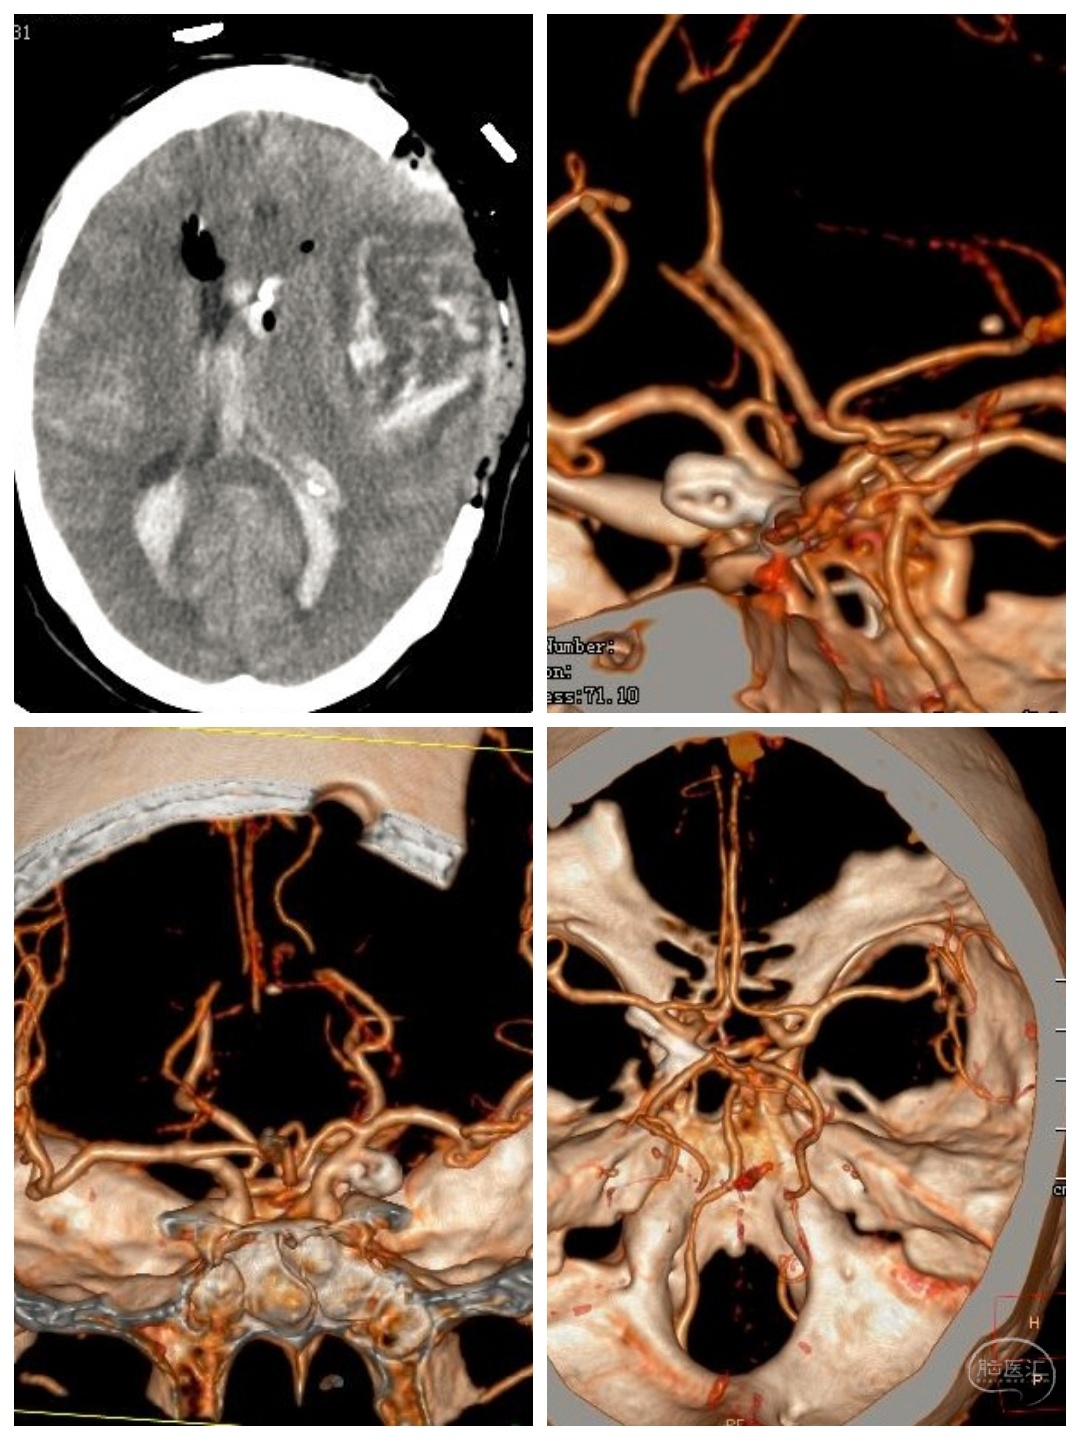

张某,男性,72岁,因“右侧肢体乏力不适三个月”入院。

CT及CTA提示左侧大脑灌注不足,左侧大脑中动脉M1狭窄。考虑此处串通支较多,予以搭桥手术。

术中游离颞浅动脉,暴露大脑中动脉M4段,行STA-MCA吻合术。

半年后患者来我科复查DSA。颞浅动脉与M4血管吻合满意,颈外动脉造影可见大脑中动脉显影,天堑造通途。。。